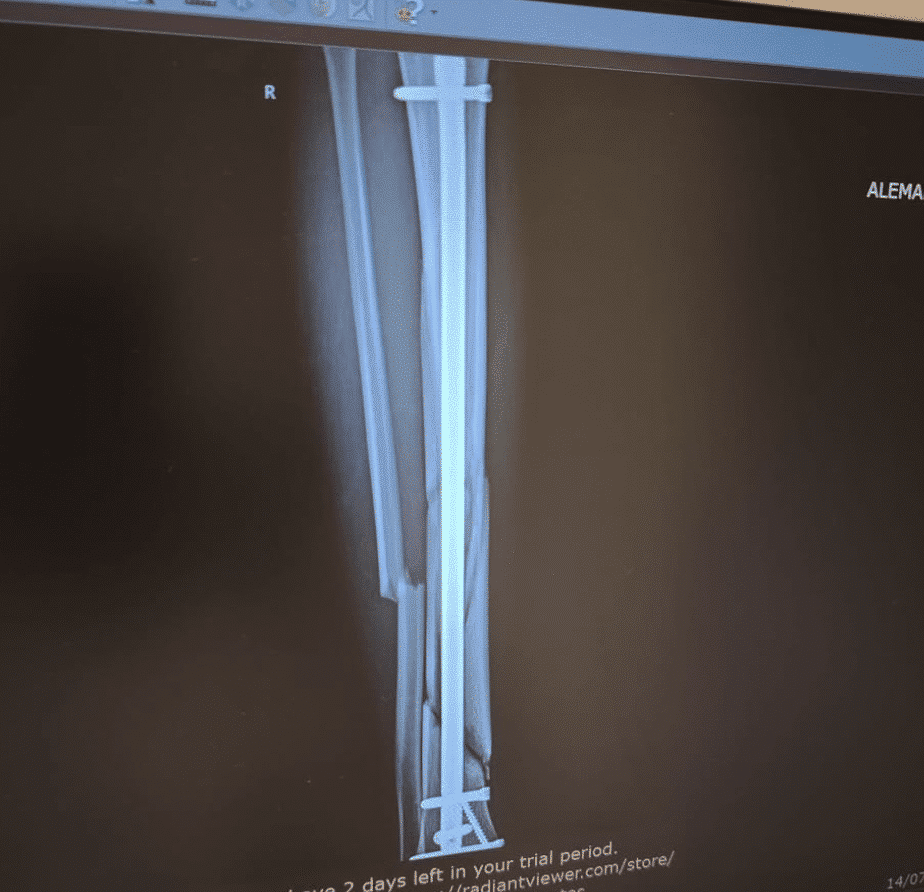

Luca Lunetta fue protagonista de un grave accidente en Assen: aquí las imágenes de su rodilla dañada.

Los exámenes en el hospital confirmaron el diagnóstico: fractura conminuta de tibia y peroné, una lesión grave que requirió una inmediata intervención quirúrgica en Groningen.

El episodio tuvo lugar en la última vuelta de la carrera, cuando Lunetta quedó envuelto en un contacto con Fernández y Furusato. Golpeado por una moto en la pierna y por otra en la espalda, el piloto del Team Sic58 Squadra Corse quedó tendido en el suelo con fuertes dolores, obligando a la dirección de carrera a interrumpir la prueba con bandera roja.